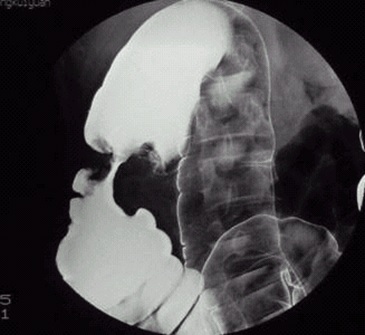

05卷-3.病史:女性,52岁,触及腹部包块3周。诊断(本题满分2.00分)

结肠癌

B.结肠癌

本题答案:B

题目解析:【该题针对“造影-结肠癌”知识点进行考核】